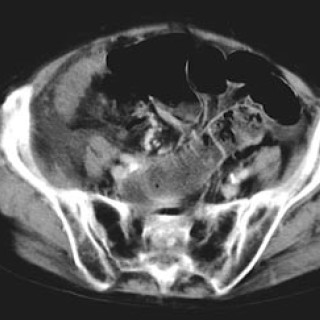

En 52 år gammel etnisk norsk mann ble innlagt i psykiatrisk akuttavdeling etter noen få uker med kraftig økende aktivitetsnivå. Han hadde vist markant endret atferd – blant annet hadde han satt seg fore å sykle åtte mil i kuldegrader og slaps. Ved innleggelsen var han irritabel og snakket fort og nærmest usammenhengende. Somatisk status presens ved innkomst samt orienterende nevrologisk status var normale. Vanlige blodprøver ved innleggelse, inklusive Hb, SR, hvite blodceller, kreatinin, natrium, kalium, ALAT, ASAT, ferritin, folat, kobalamin, FT4, TSH, var alle innenfor referanseområdet...